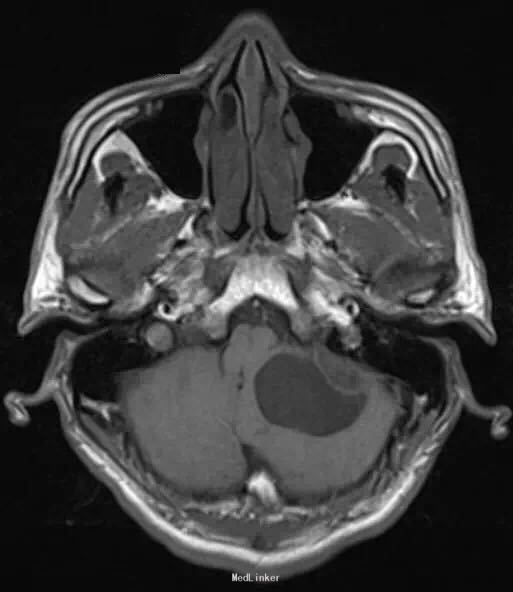

26 岁男性,头疼,恶心,出现加重性嗜睡一个月。

脑 MRI 检查示,左小脑半球一囊性成分为主的病灶,边界清楚,增强扫描见明显强化壁结节。可有轻度血管源性水肿和轻微局部占位效应,临近的四叠体和中脑周围池受压。GRE 序列上未见相关性出血的征象

诊断:小脑血管母细胞瘤。 整块切除 + 术前栓塞术。 可辅助立体定向放射外科技术。